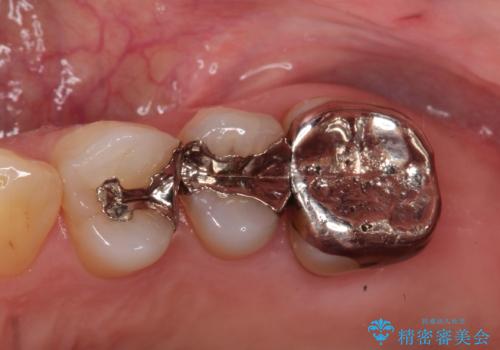

銀歯からセラミックへ。右上奥歯の精密根管治療と審美修復

担当医 河口智英